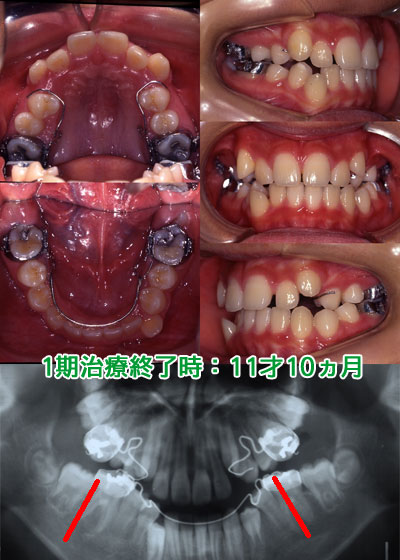

レントゲンで下顎臼歯が前方に傾斜し犬歯、小臼歯が萌出するスペースが不足し、下顎前歯の叢生を治しても通常なら4本の永久歯を間引きする抜歯症例となります。また、前歯の咬み合わせが深く(下の前歯が隠れている)下顎が後退し後に顎関節症にも移行する可能性が高い症例です。

下顎は3Dリンガルアーチ(人目には見えない内側の矯正装置)を用いて下顎大臼歯の前方への傾斜を修正し大臼歯を整直させることにより、犬歯、小臼歯が萌出するスペースを獲得します。下顎前歯の叢生も改善し、非抜歯症例へと咬合誘導を行います。上顎は3Dクワッドヘリックス(人目には見えない内側の矯正装置)を用いて上顎大臼歯の捻転の修正と犬歯間を拡大することで犬歯、小臼歯が萌出するスペースを獲得します。また、前歯の咬み合わせも浅く(下の前歯が見えてきています)下顎の後退も改善され顎関節症も改善されてきました。

最終的にフルブラケットを各歯牙に装着し仕上げを行い矯正治療を終了します。通常なら4本の小臼歯を間引きする症例ですが当医院では非抜歯咬合誘導を行うことで下顎の臼歯部が整直し各歯牙の歯軸は平行性が保たれ、咬合力に強い症例と仕上げることが出来ました。歯槽膿漏・虫歯になりにくい咬み合わせで、この咬合を維持するようにメインテナンスを行う事で8020(80歳で20本の歯を残す)また、6024(60歳で24本歯を残す)が達成出来ます。また、顎の骨の中で歯牙の根先の移動が少ない為、歯根歯根吸収も最小限に抑えられます。また、前歯の咬み合わせも浅く顎関節症も改善されてきました。

アングルIII級症例(非抜歯) 初診時年齢:11才11ヵ月 男性 over jet 4.7㎜ over bite 1.5㎜ 臼歯関係:右側 アングルIII級 左側 アングルIII級

小野の回帰方程式 近遠心幅径の総和

X'=24.2

3・4・5番幅径総和の予測値

Y=23.7 Y`=22.9

ディスクレパンシー

上顎 -2.9 -3.1

下顎 -2.2 -0.8

アーチレングスディスクレパンシーは

上顎-6.0mm、下顎-3.0mm

治療方法

動的治療期間:3年4ヵ月

1期治療:1年1ヵ月

下顎 3DL(5)

上顎 3DQ

2期治療:FBS 2年3ヵ月

抜歯部位 38・48番